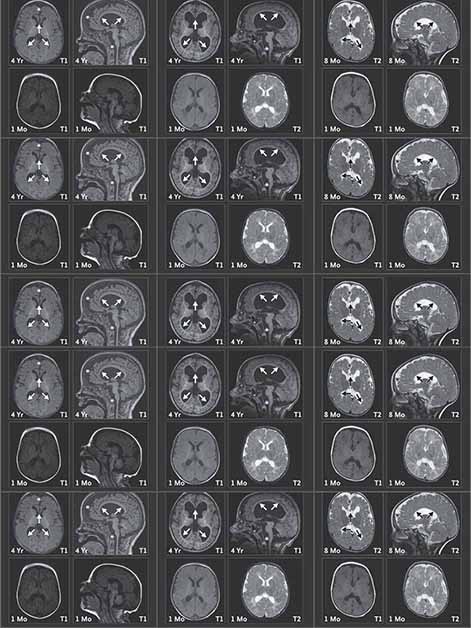

לאחר שנוצר הקשר הראשוני ב-2019, החלו שיחות זום חודשיות בין חוקרים ברחבי העולם ובין בריאן ברודבנט, אביה המסור של אמה. המדענים הדגישו בפניו את הקושי ללמוד ממקרה בודד, אך פריצת דרך חשובה התרחשה ב-2021, כשהתקבל מייל מקבוצת מחקר צרפתית שנתקלה במקרה בילד נוסף שהיה חסר לו עותק של הגן. שנה לאחר מכן, נמצא מקרה שלישי בצרפת, ואף שתחילה נדמה היה שהמקרים אינם דומים, שיחת זום גורלית שינתה את התמונה. "בשיחה השתתפו החוקרים ומשפחות הילדים ונעזרנו בפוסט-דוקטורנטית מצרפת שעבדה בבוסטון שיכלה לתרגם מצרפתית לאנגלית", מתאר פרופ' אוליצקי. "בפעם הראשונה שהמשפחות ראו זו את זו הן זיהו מיד שלילדיהן מאפיינים דומים מבחינה נוירולוגית וגם דמיון פיזי. בדיקות מעבדה הראו כי בתאיהם של הילדים, כמו שראינו בעכברים, מצטברות רמות גבוהות של CHD2. סריקות MRI הראו כי בשנים הראשונות לחיי הילדים ישנה פגיעה מחריפה בחומר הלבן במוח, שאחראי לעדן ולדייק את העברת האותות בין תאי העצב. כעת לכל משפחה יש אבחנה – תסמונת עיכוב שכלי התפתחותי ואפילפסיה הנגרמת מעותק חסר של הגן צ'ייסר – ויש להן גם קשר לעוד משפחות שמתמודדות עם המחלה. ועדיין, לא יהיה סוף טוב לסיפור עד שנמצא טיפול".